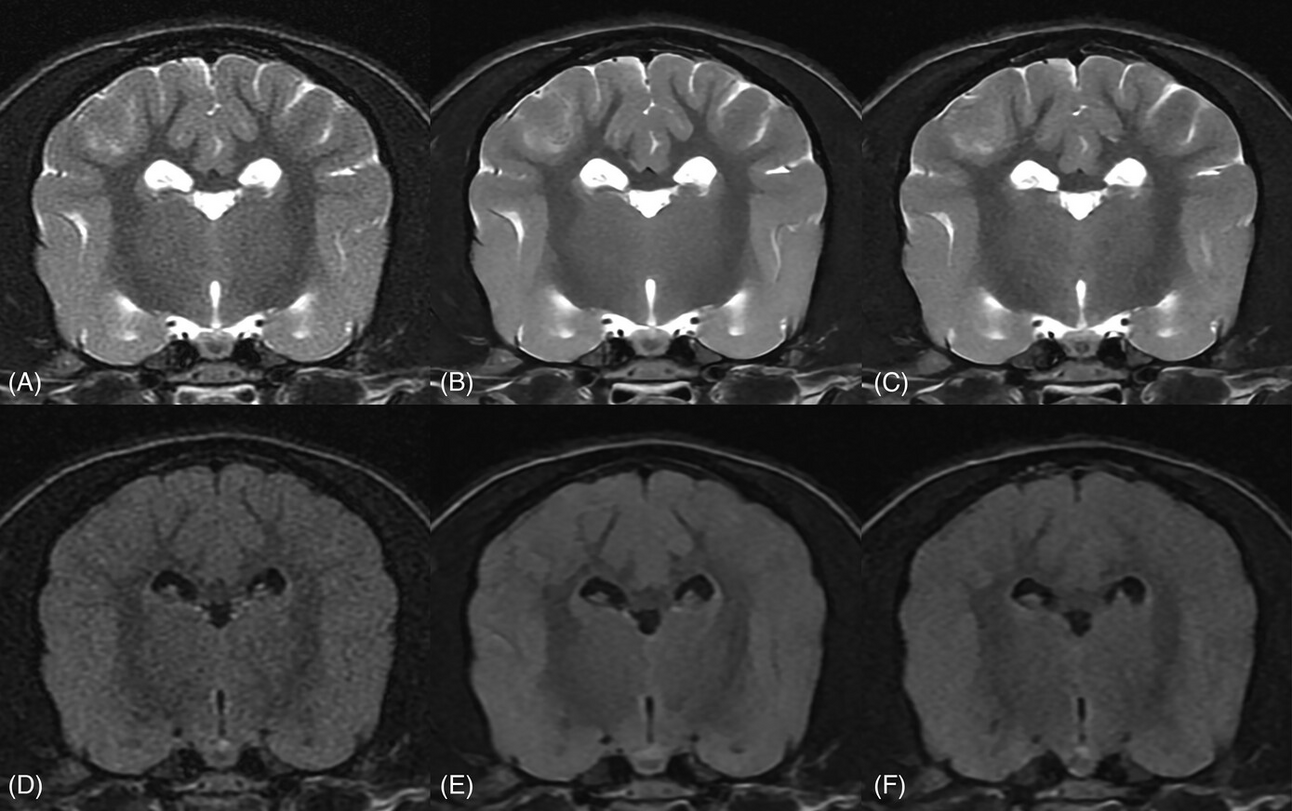

Deep learning imrproves MRI signal

VRU 2023 64(5): 873-880